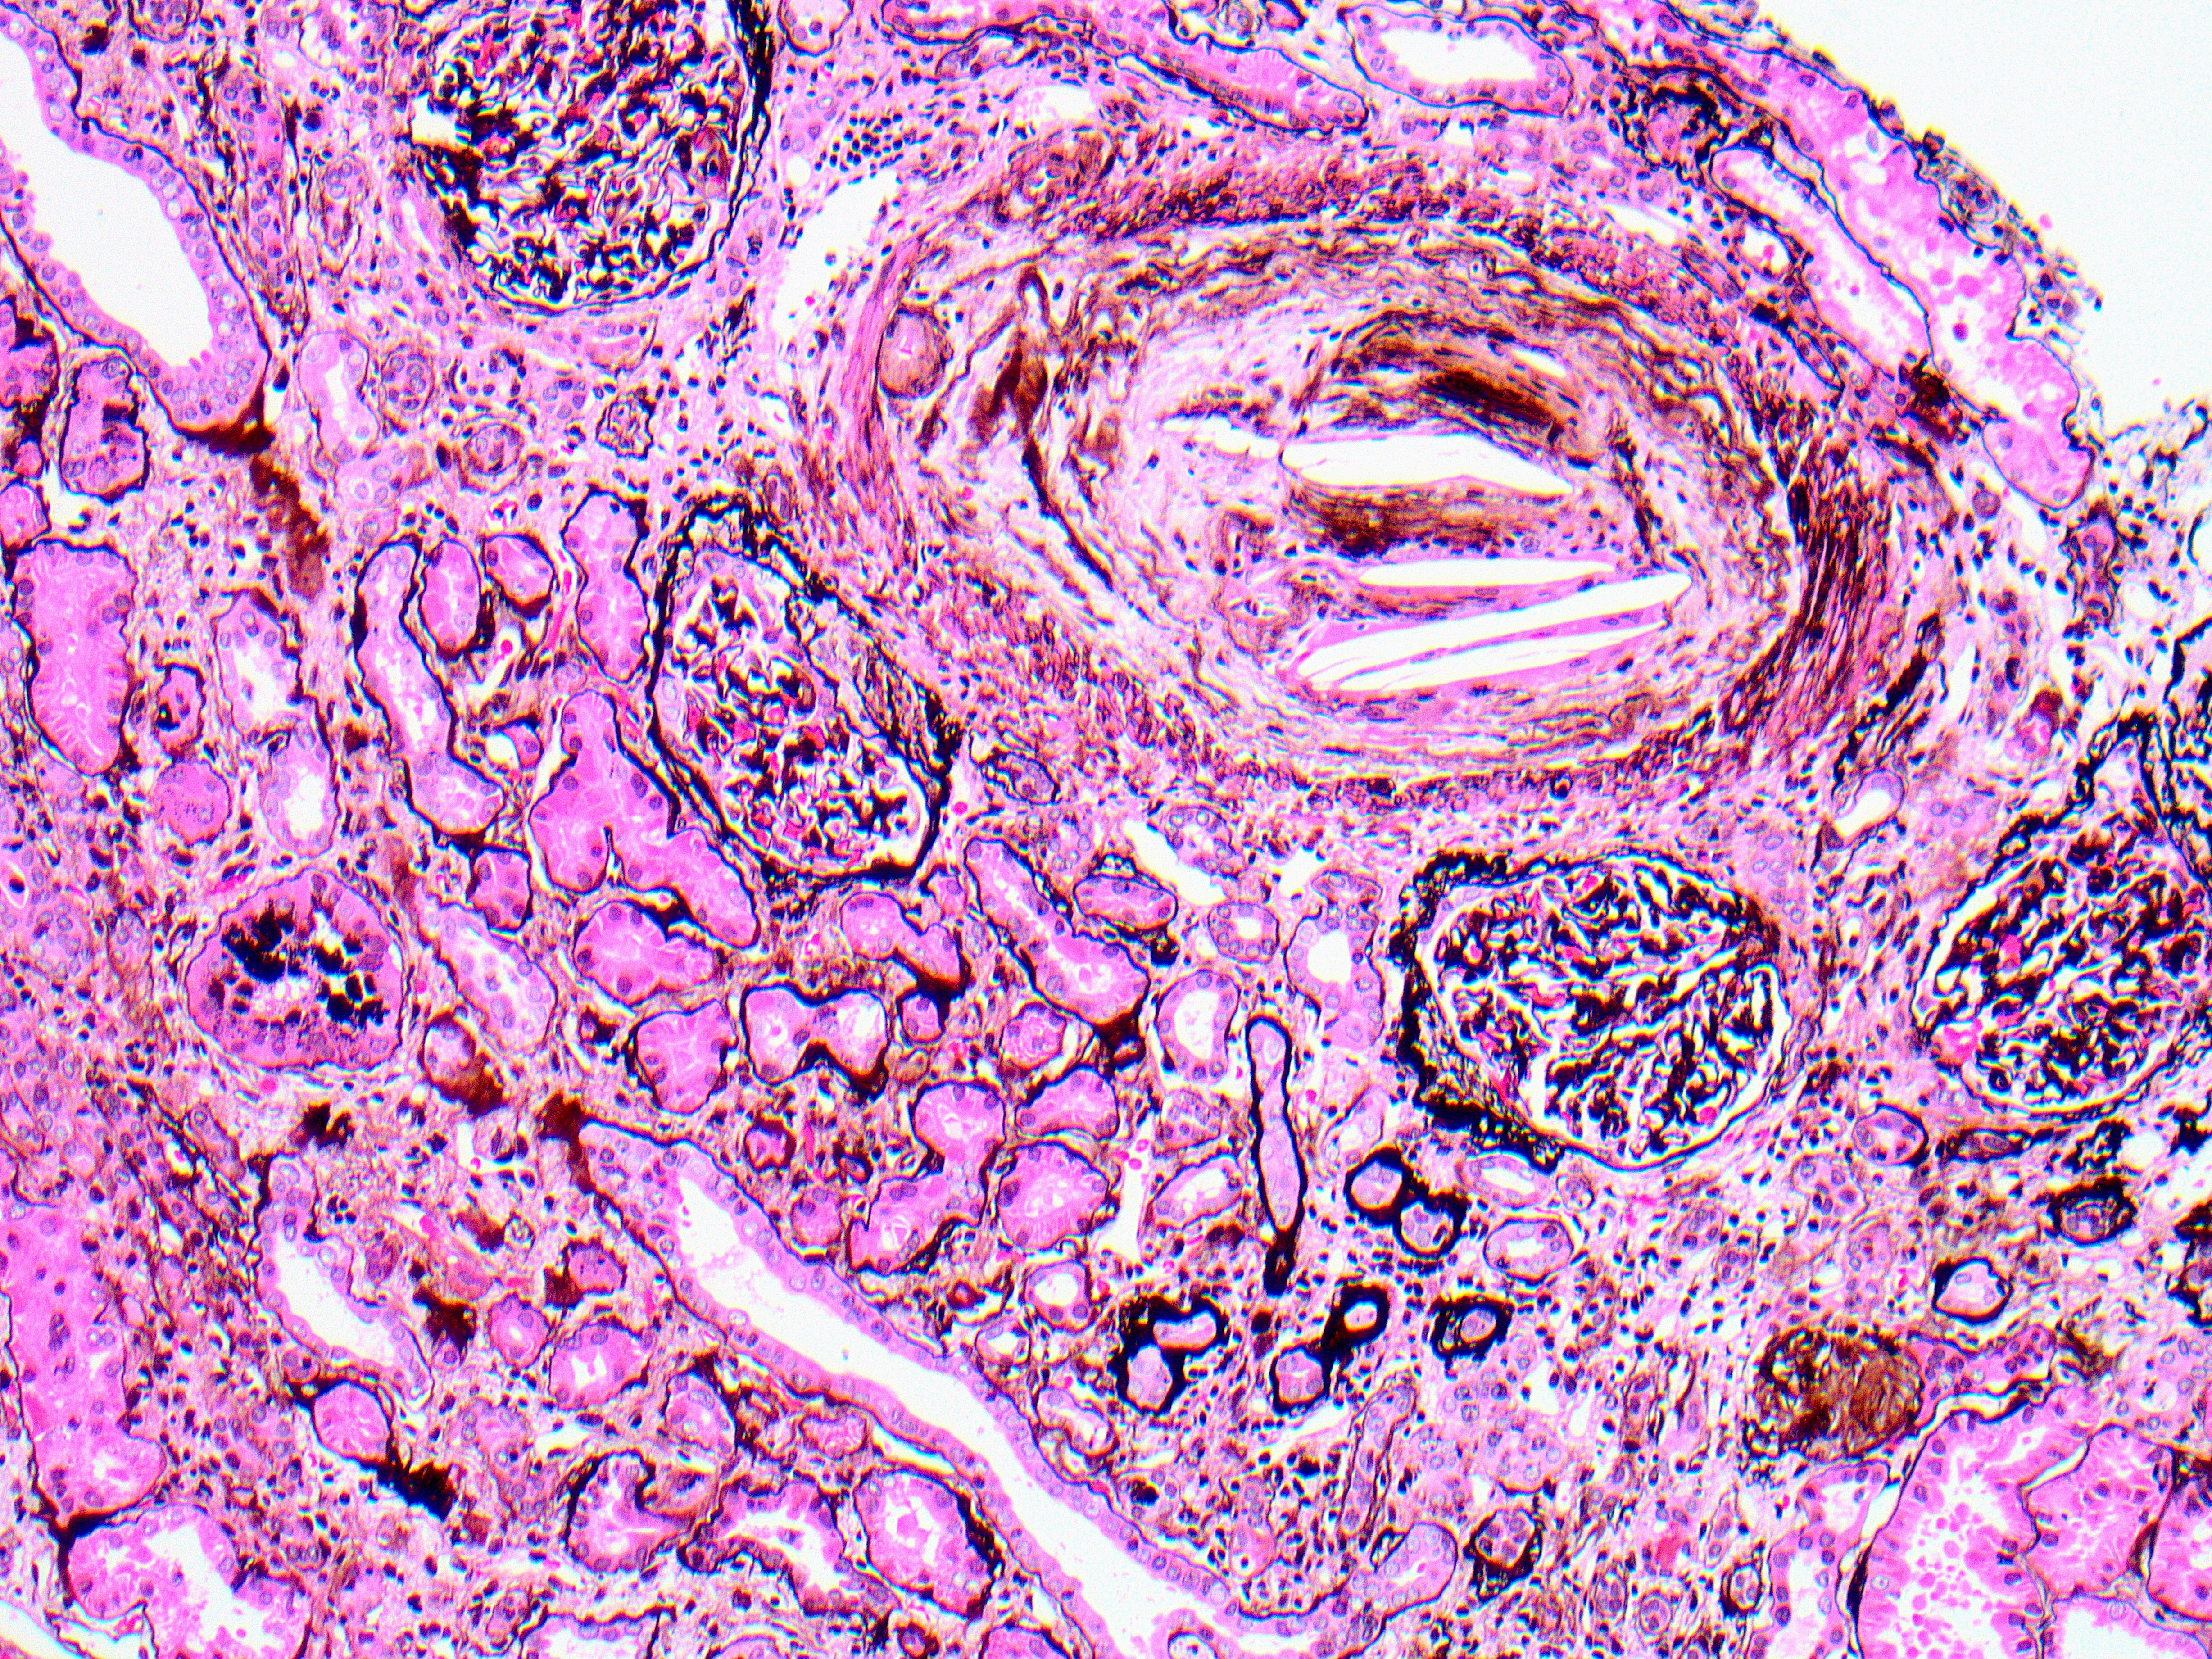

On medium power a cross section of an interlobular artery shows multiple intraluminal cleft-shaped spaces, reflecting the empty spaces left after the dissolution of cholesterol by standard processing (Jones silver Fig a). Chronic ischemic glomerular and tubulointerstitial injury is also evident by focal periglomerular fibrosis and tubulointerstitial scarring, respectively. High power of the same artery shows intimal fibrosis and mild cellular proliferation with occasional mononuclear cells and multinucleated giant cells (arrow) surrounding cleft-like spaces, representing a dissolved cholesterol embolus (PASH Fig b).